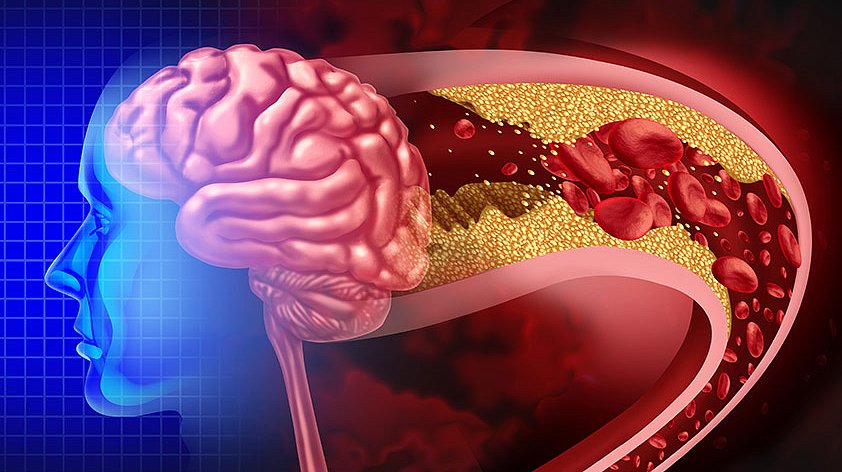

Хроническая ишемия головного мозга и лейкоареоз: симптомы и лечение